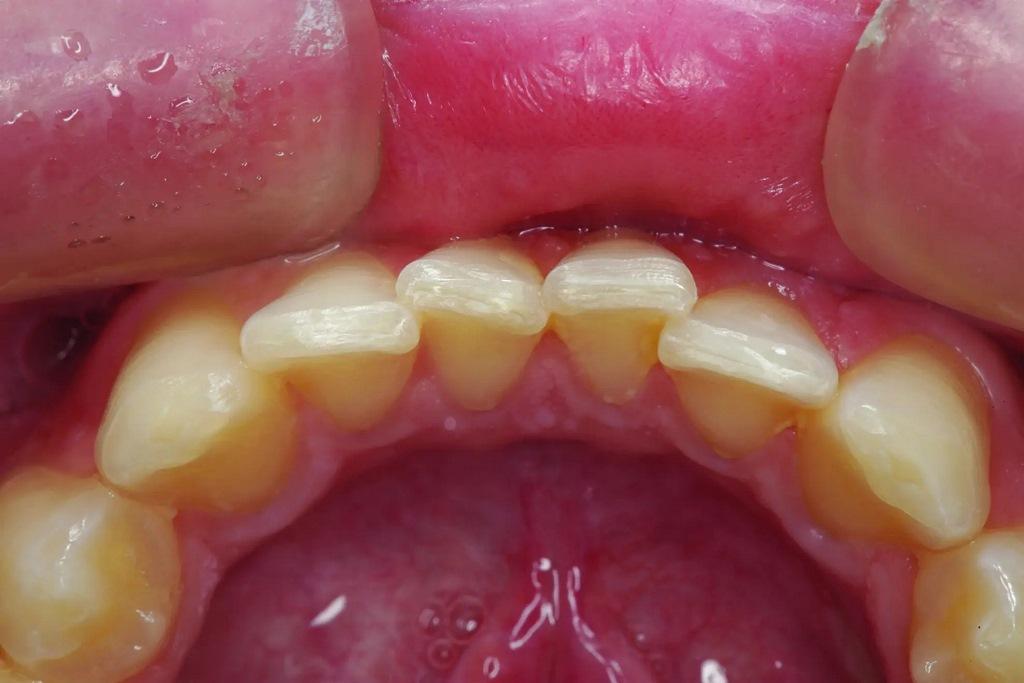

А как насчет выравнивания зубов-антагонистов? На режущих краях зубов 31 и 41 (фото 2) наблюдался чрезмерный износ. Со стороны резцов был виден значительный износ всех краев нижней челюсти из-за окклюзионного заболевания, которое часто наблюдается, но не лечится (фото 3). Также зуб 41 располагался на лицевой стороне таким образом, что при выступающей экскурсии он преждевременно соприкасался с небной поверхностью зуба 11, создавая дополнительную нагрузку как на небную поверхность, так и на резцовый край зуба 11, прежде чем соединиться с остальной частью переднего сегмента верхней челюсти. Это демонстрирует, что решение этих проблем реставрационными методами включает в себя нечто большее, чем просто исправление сколов композитной реставрации.

Фото 3: Резцовый вид показывает, что зуб 41 был наиболее расположенным к лицу резцом нижней челюсти в форме дуги.